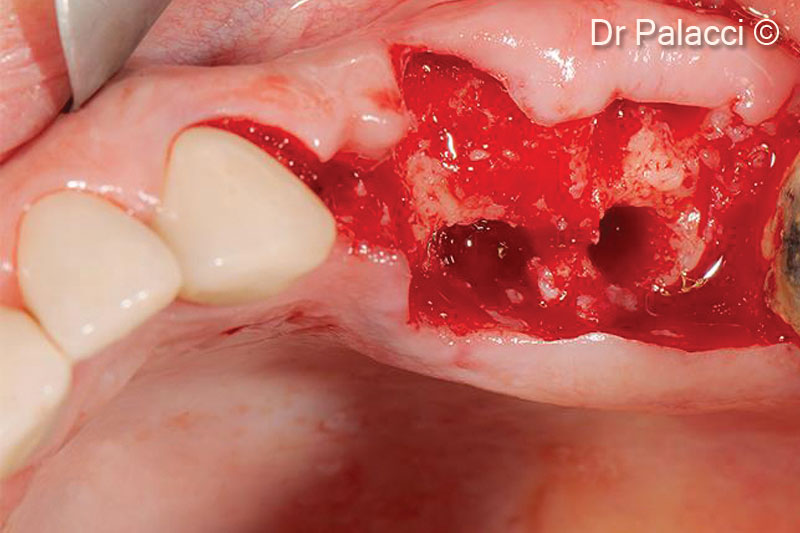

Răng bị nhổ, toàn bộ xương môi bị mất có thể thấy rõ sự tiêu xương nghiêm trọng